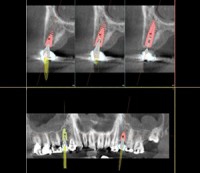

3D Cone Beam Imaging

3D volumes are used to assess bone quality to implant area and to view all the surrounding anatomic structures through different planes.